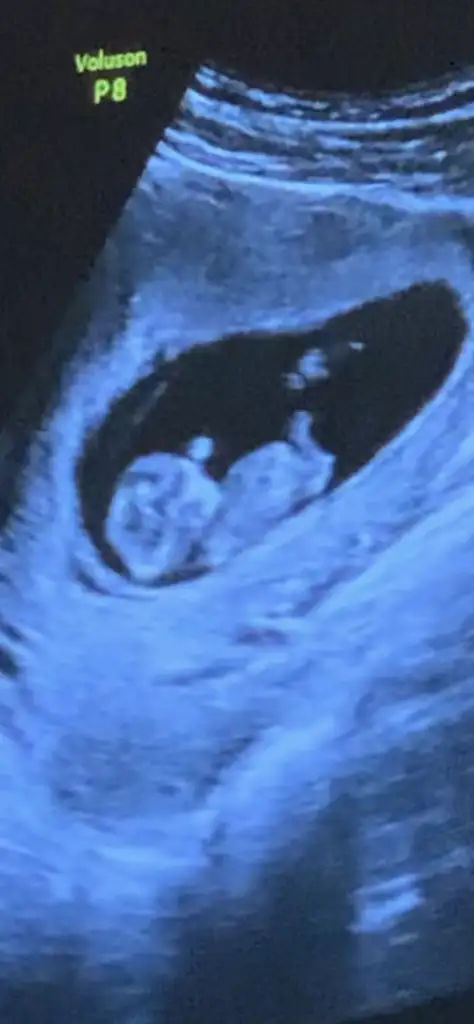

dr soylemeden siz gorun genital nub teorisi ( bebegin cinsiyeti)

Doktorumun söylediği bir tüyomda var cinsiyet tahmini ile ilgili. Varsa daha keseyi gördüğünüz zaman ki ultrasonlarınız yardımcı olurum😘

Merhaba banada yardımcı olurmusunuz lütfen nubu görünmedi belki keseden belli olur